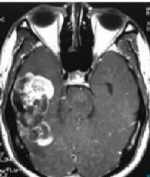

罕見(jiàn)!巨大橫紋肌腦膜瘤完全鈣化及鑒別診斷分析 關(guān)鍵疾?。?a href="http://m.akellydesign.com/tags/so/腦膜瘤-4-1.html" target="_blank">腦膜瘤 現(xiàn)病史【一般資料】 女性,50歲, 【主訴】 頭痛伴惡心、嘔吐、步態(tài)不穩(wěn)2個(gè)月余 【現(xiàn)病史】2個(gè)月前無(wú)明顯誘因出現(xiàn)惡心、嘔吐,休息后緩解,逐漸出現(xiàn)行走不穩(wěn),無(wú)意識(shí)障礙,四肢抽搐等不適,現(xiàn)住院進(jìn)一步治療。 【既往史】既往無(wú)特殊 【查體】 T:36.2℃,P:74次/分,R:20次/分,BP:130/70mmHg。神志清楚,雙側(cè)瞳孔等大等圓,直徑約3 mm,對(duì)光反射靈敏,無(wú)視野缺損和偏盲;腦膜**征陰性,左上肢肌力III級(jí),其余肢體肌力V級(jí),生理反射存在,病理反射未引出 【輔助檢查】 CT示右側(cè)顳葉可...